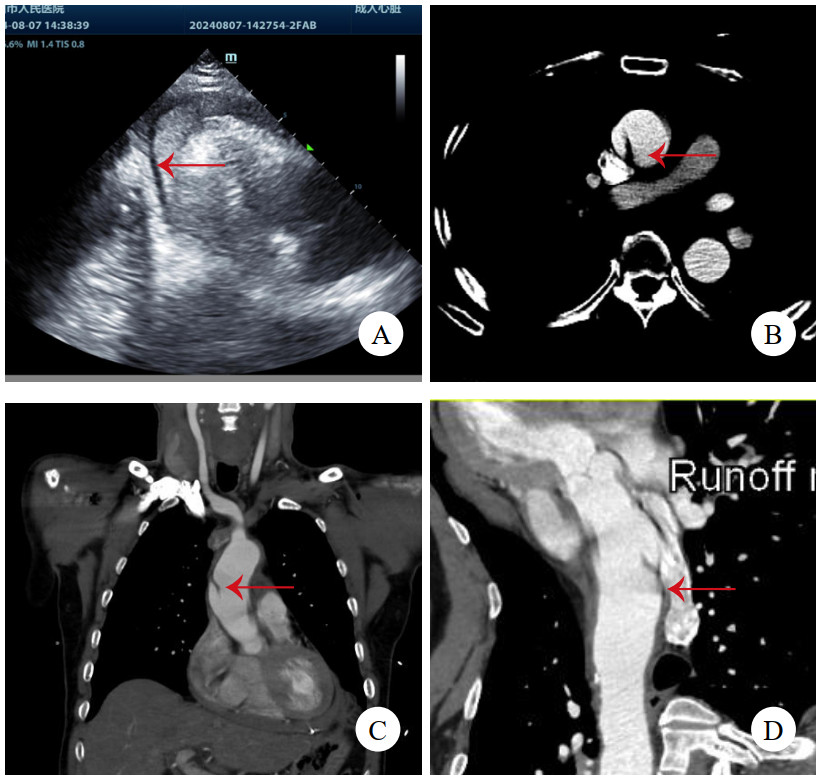

病例4,男,63岁,因“活动后胸闷、气促6年,加重1月”入院。TTE提示二尖瓣前叶A2区腱索断裂伴脱垂、重度返流,主动脉瓣重度返流,三尖瓣中度返流,左心室显著增大,左心室舒张末期直径86 mm,心功能减低,中重度肺动脉高压,升主动脉内径增宽直径43 mm。冠状动脉CTA提示双侧冠状动脉无显著病变,少量心包积液,未见主动脉根部病变(图 4A)。术前准备后,择期手术,术中见主动脉前壁窦管交界水平一长约2 cm的内膜撕裂符合LIT。仔细观察切除标本(图 4B),见内膜裂口边缘光滑,考虑为陈旧性改变。予行Bentall加二尖瓣机械瓣置换加三尖瓣成型术。术后康复顺利,规律抗凝随访1年。

注:A为冠状动脉CTA,未见异常;B为切除的主动脉壁,箭头示内膜裂口 图 4 例4患者CT影像及主动脉壁照片